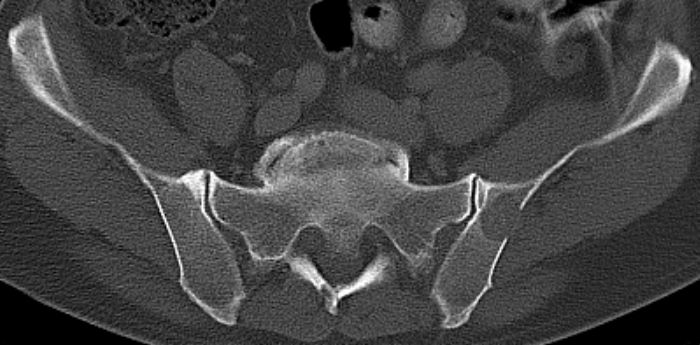

Asymptomatische Lyse am linken Darmbein![]() | ||||